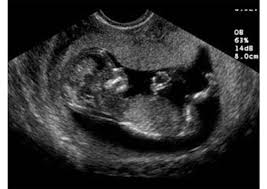

الحمل في الشهر الثالث بالصور. الحمل في الشهر الثالث الاسبوع 9 13 من الحمل الاسبوع التاسع من الحمل. نصائح للحامل في الشهر الثالث. تطورات الجنين في الشهر الثالث.

ارتدي الأحذية الطبية التي تريح ساقيك ولا ترتدي الكعب المرتفع. كما وت صاب الأم بدوران ودوخة بسبب الحمل في هذا الشهر ولكن سرعان ما تنسى الأم هذا الألم عند مشاهدتها شكل جنينها لذا سن طلعكم هنا على شكل الجنين فى الشهر الثالث بالصور. إن البطن في الحمل الثاني أو الثالث يظهر بشكل أسرع من ظهوره في الحمل الأول وذلك لأن عضلات البطن والرحم اعتادت على ذلك.

الحمل في الشهر الثالث بالصور الحمل في الشهر الثالث. اصابع يده وقدمه تزيد طولا على الرغم من انها مندمجة مع بعضها للآن. بداية تواجه الحامل في هذا الشهر مجموعة من المشاكل أو الأعراض التي تسب ب لها كثيرا من الانزعاج منها.